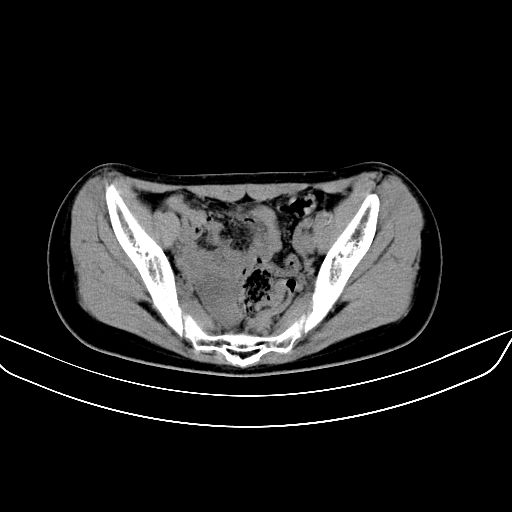

以下是引用zsl6918在2008-7-11 21:40:00的发言:[br]双侧骶髂关节骨质破坏以下三分之一为主,符合强直性脊柱炎表现

以下是引用zhangzhongshou在2008-7-11 21:41:00的发言:[br]患者是女性,hla-b27抗原(—),首先不太考虑强直性脊柱炎,建议查类风湿因子,骶髂关节改变考虑类风湿性关节炎可能性大,建议进一步检查。